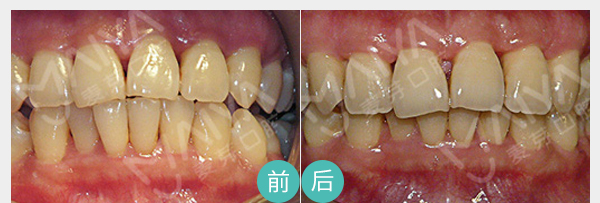

麦芽脱敏治疗

麦芽龈下刮治

麦芽显微根管治疗